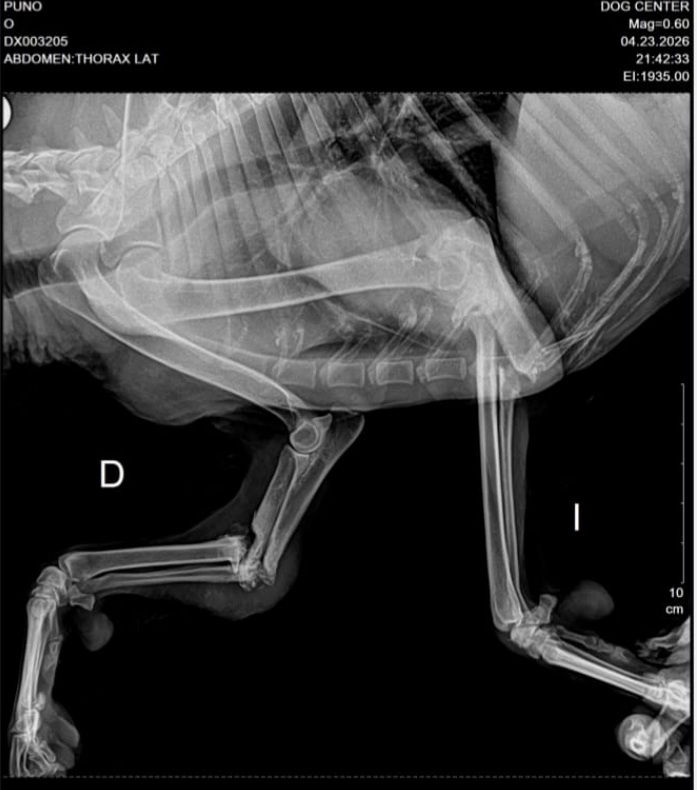

Partieron hace como 15 días y llegaron hasta la Clínica Veterinaria Doc Center, donde le hicieron los exámenes necesarios para determinar que Puno podrá volver a caminar con normalidad en unas semanas.

No pudieron hacerse las dos cirugías al mismo tiempo, ¿la razón?… sufría de arritmia cardiaca.